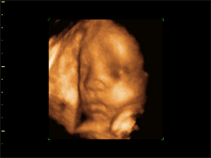

3D                          4D                             3D

© BabyView, 2006. All Rights Reserved.